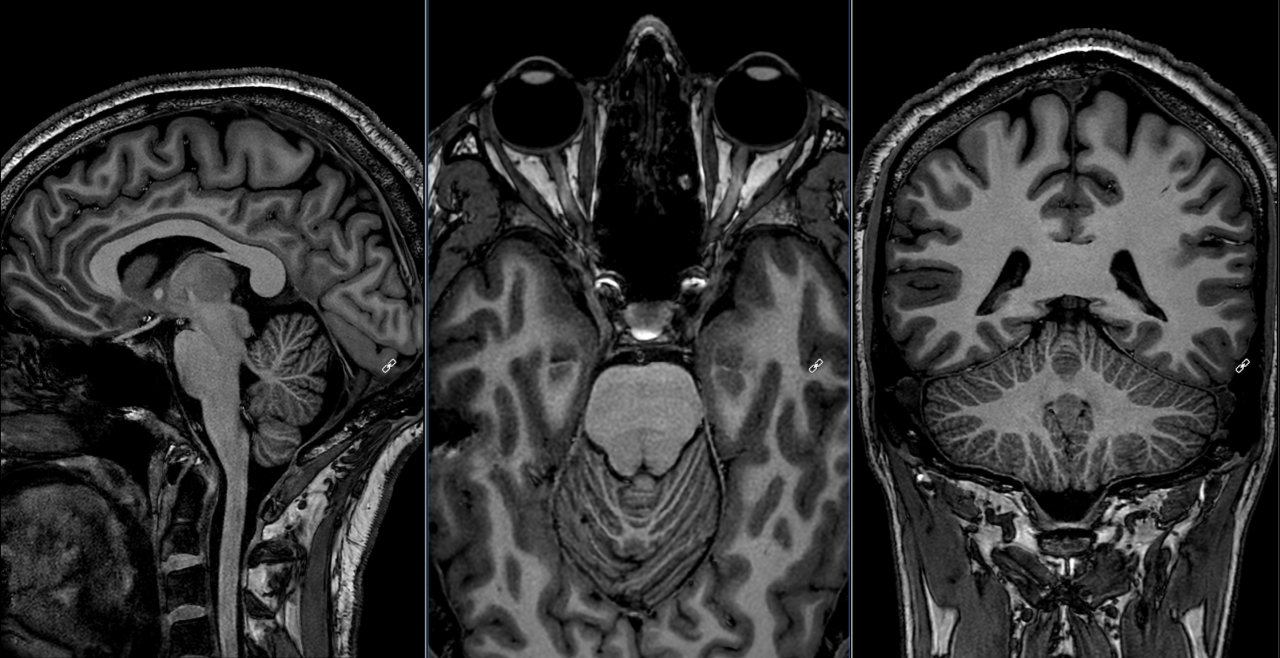

Unlocking Ultra‑High‑Resolution 3T MRI at NeuRA Imaging

NeuRA Imaging has introduced a powerful new AI‑driven MRI capability, acquiring the highest‑resolution anatomical images ever acquired on a 3T MRI scanner.

A major software upgrade at NeuRA Imaging has delivered unprecedented ultra‑high‑resolution brain scans on a 3T system.

NeuRA Imaging is among the first research centres in Australia to implement SmartSpeed Precise [1] on a 3T system, a next‑generation dual‑AI reconstruction technology that dramatically boosts image quality and scanning efficiency.

With the ability to sharpen images by up to 80 percent and accelerate acquisitions by as much as threefold, SmartSpeed Precise represents a genuine leap forward in clinical and research imaging.

Using SmartSpeed Precise, researchers at NeuRA Imaging have now achieved 0.27 mm isotropic structural brain scans in under 13 minutes, a level of microscopic anatomical detail normally reserved for ultra‑high‑field MRI or multi‑hour, multi‑session imaging protocols.

Capturing this kind of resolution on a standard 3T system, and doing it in a routine single-session scan, marks a leap forward in 3T MRI for human neuroimaging.

For researchers, this new capability means shorter, more comfortable sessions for participants and faster access to high‑quality structural data. Many fine‑grained anatomical details that once required lengthy protocols, or weren’t feasible on 3T at all, can now be resolved in a single efficient scan.

Images acquired at NeuRA Imaging, thanks to Iain Ball and Brendan Moran.

PRECISE reconstructed to 0.27mm iso acquisition parameters:

- Acq voxel size = 0.54 mm iso

- scan time = 12:49 min

- TR/TE = 8.3/3.7 ms, TI = 850 ms

- multishot TFE = 157, FOV = 242

- CSENSE = 2